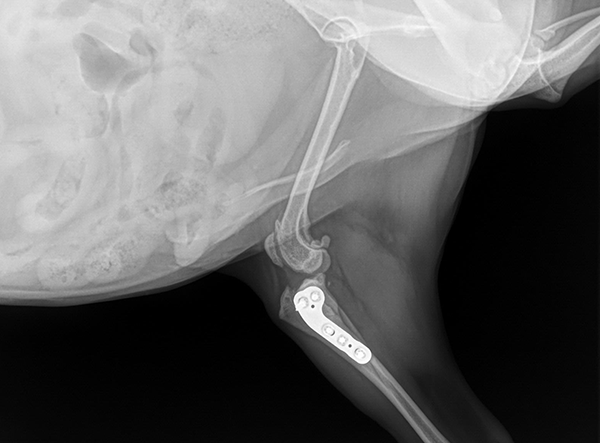

Today’s patient was a petite, 5 kg mixed-breed dog with a cruciate ligament injury. To address the biomechanical demands and ensure long-term stability, a 2.0 mm LeiLOX TPLO Plate was used. The miniaturized plate design allowed for precise anatomical fit without compromising strength.

The surgery was completed smoothly, and postoperative radiographs confirmed excellent alignment and fixation. With controlled rehabilitation, the patient is expected to regain full mobility and enjoy a pain-free return to daily activity.

Implant Used: 2.0 mm LeiLOX TPLO Plate Stainless Steel Plate (also available in Titanium)